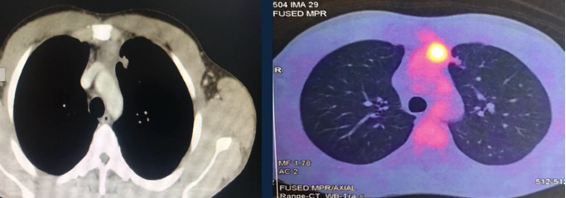

A 32-year-old man was referred with a diagnosis of an extragonadal germ cell tumor in the anterior mediastinum. Initially, he was treated with four cycles of chemotherapy (bleomycin, etoposide phosphate, and cisplatin), after which a PET-CT demonstrated a persistent hypermetabolic mass (SUV max 7.8) in the anterior mediastinum measuring 48 x 32 x 70 mm, without other metabolic abnormalities. Alpha-fetoprotein (AFP), LDH, and human chorionic gonadotrophin serum levels were normal. A radical surgical resection was recommended due to persistent residual disease. It was performed via a sternotomy with mediastinal tumor resection, pulmonary segmentectomy, and left diaphragm plication, due to resection of the involved phrenic nerve. The pathology results showed an embryonal carcinoma, 90 x 70 x 40 mm, with lung parenchyma involvement and 24% necrosis. There was no lymphovascular invasion, 1 of 4 lymph nodes had metastasis, and the margins were negative. Markers CD117 and CD30 were positive, AFP was negative. The patient recovered well. He was discussed in a tumor conference and was recommended to undergo adjuvant chemotherapy followed by bone marrow transplant.

PET – CT: Persistence of a hypermetabolic residual mass (SUV max 7.8) of 48 x 32 x 70 mm is observed in the anterior mediastinum.